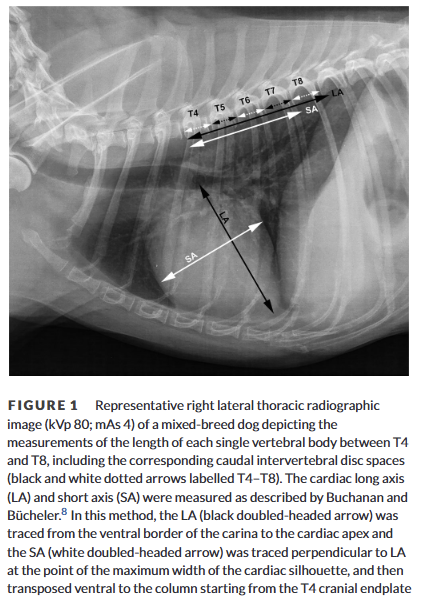

How is heart to single vertebra ratio (HSVR) calculated?

What is the advantage over VHS?

A

Similar to VHS - add together length and width of cardiac silhouette then keep subtracting length of one normal vertebra between T4-8 (including caudal interveretbral disc space)

May be more useful in dogs with vertebral body abnormalities

Which vertebra has higher accuracy for calculating heart to single vertebra ratio?

a) T4

b) T5

c) T6

d) T7